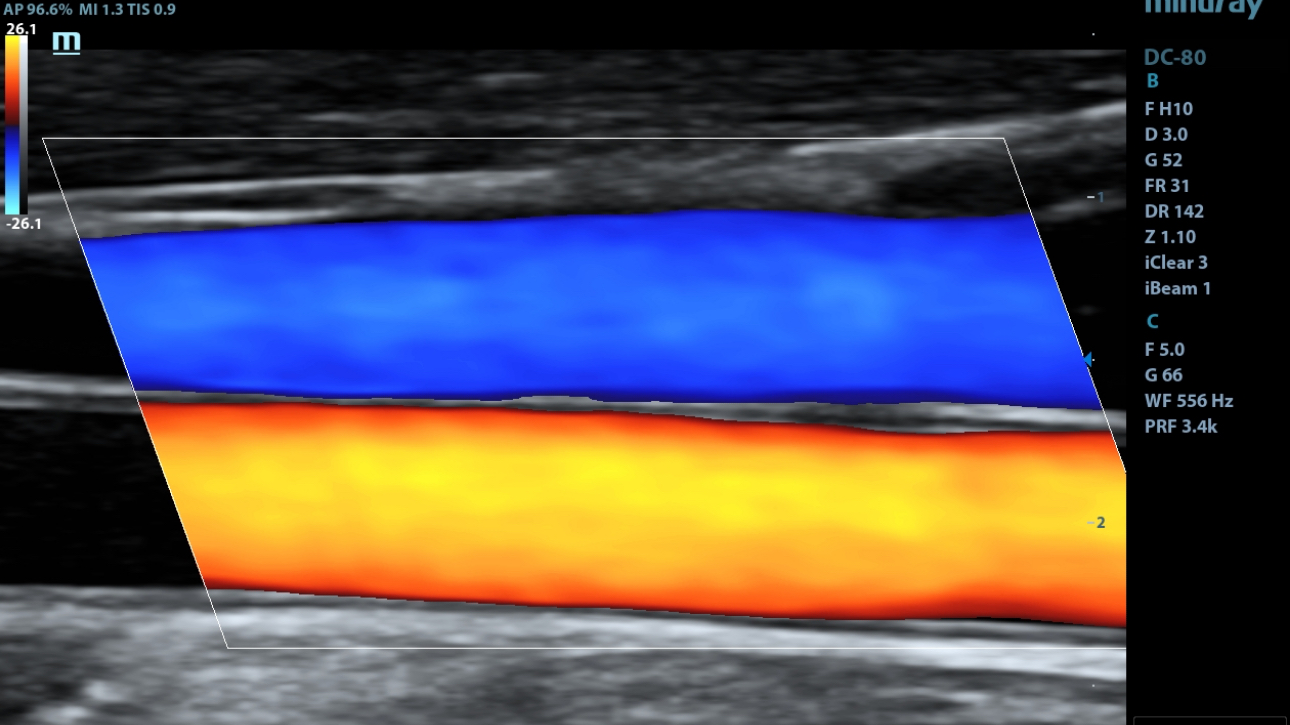

Smart Track

ItŌĆÖs Mindray unique feature to reduce repetitive, time-consuming scanning steps in vascular exams. Smart Track provides intelligent and real-time vessel tracking and real-time image optimization of Color and PW.